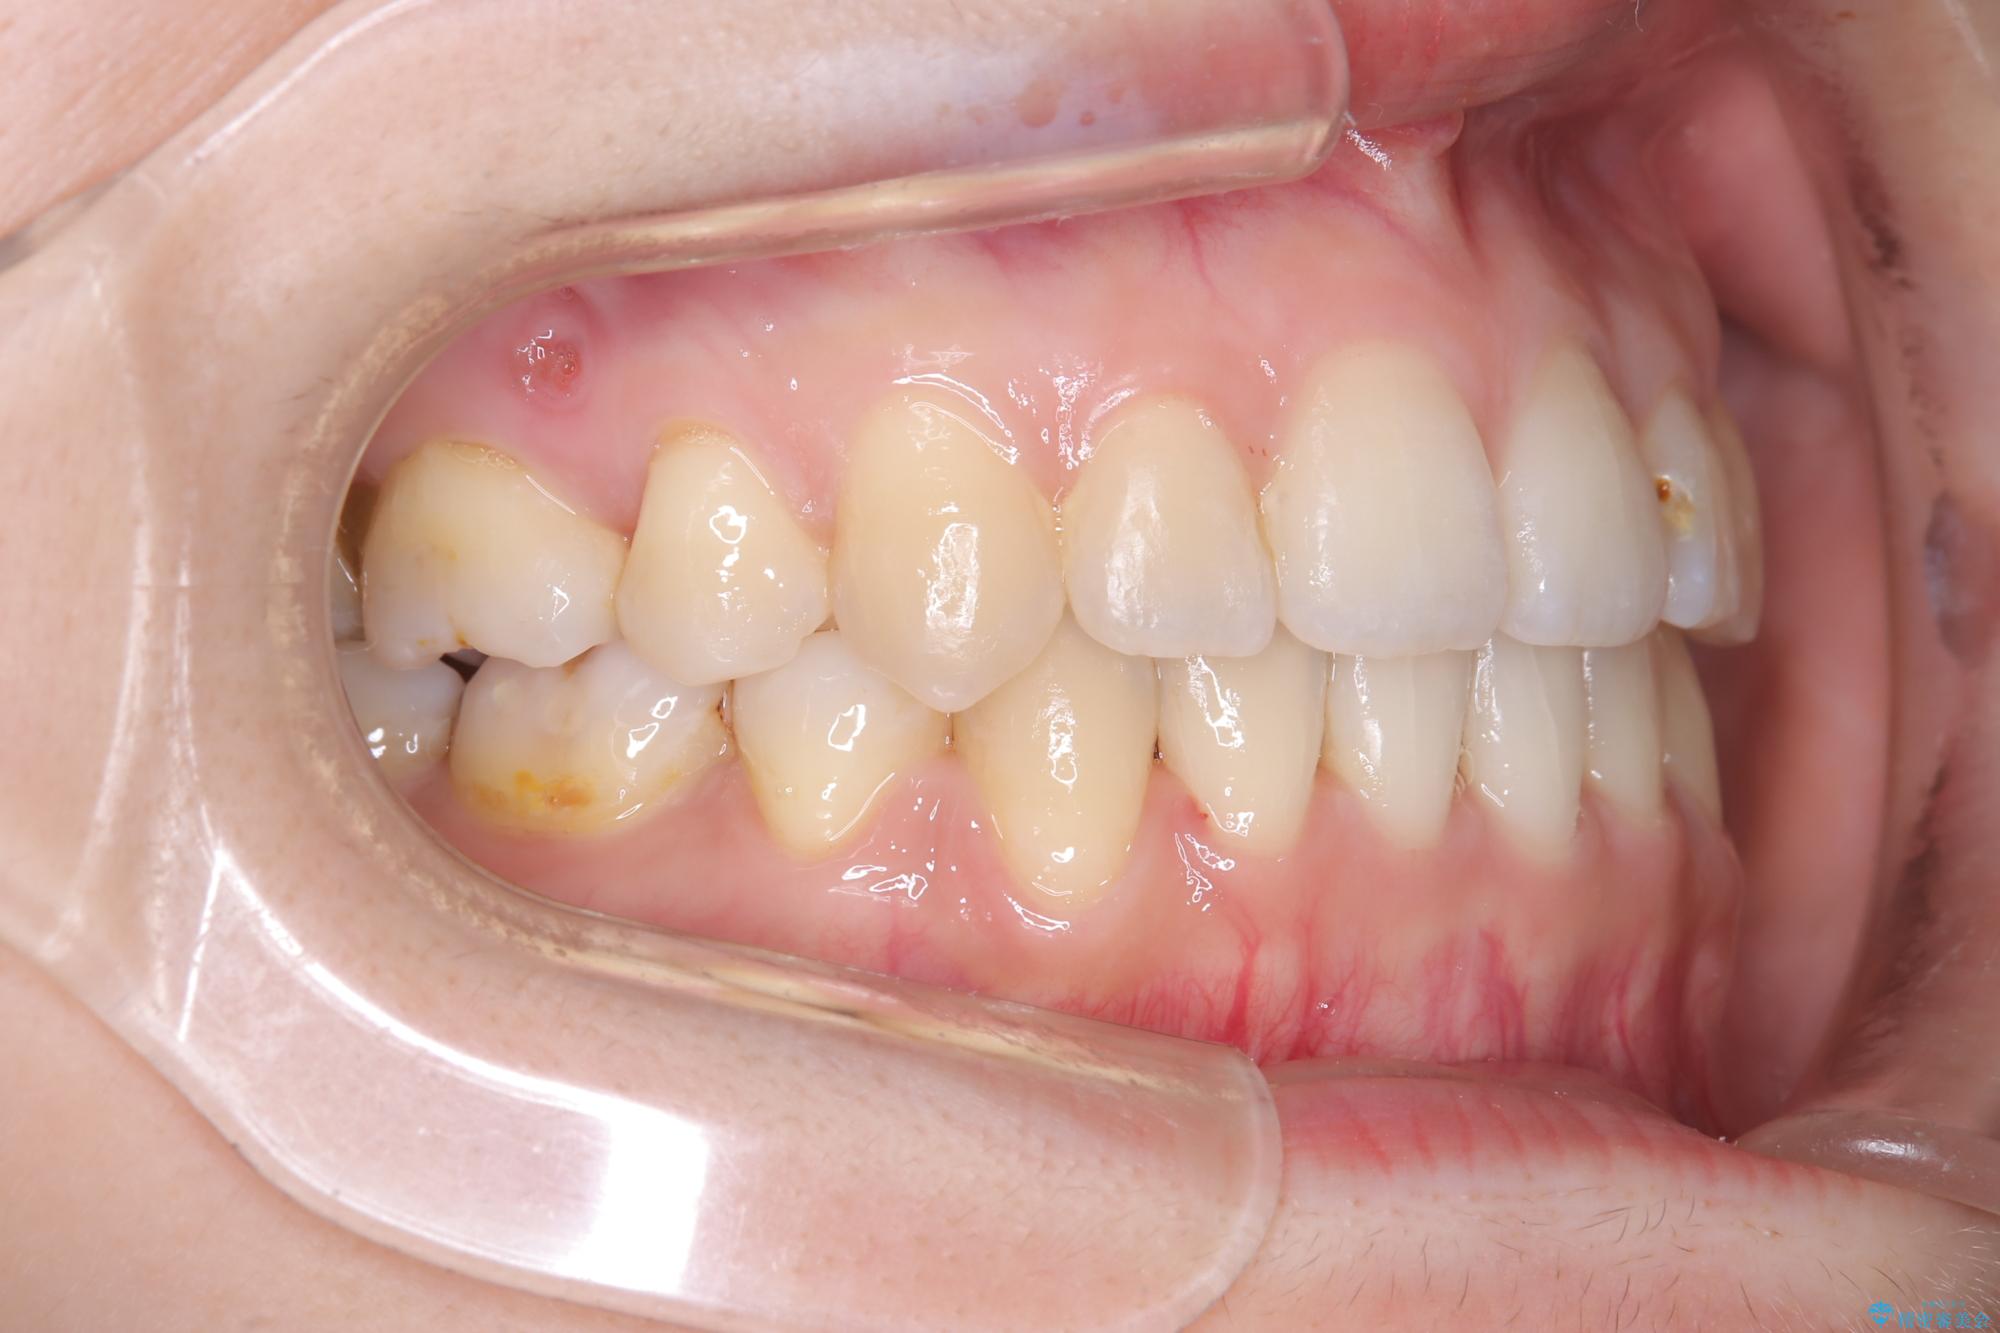

- 主訴:口元を下げて前突感を無くしたい、下の歯の凹凸も無くしたい

右側第二小臼歯、左側第一小臼歯、下顎両側第一大臼歯を抜歯しワイヤ-矯正を行いました。

骨格的顎の変位を認めたため、顔貌に対しピッタリ上下の歯の正中を合わせることは難しいと説明し、上下左右計4本小臼歯を抜歯しワイヤー矯正治療を行いました。